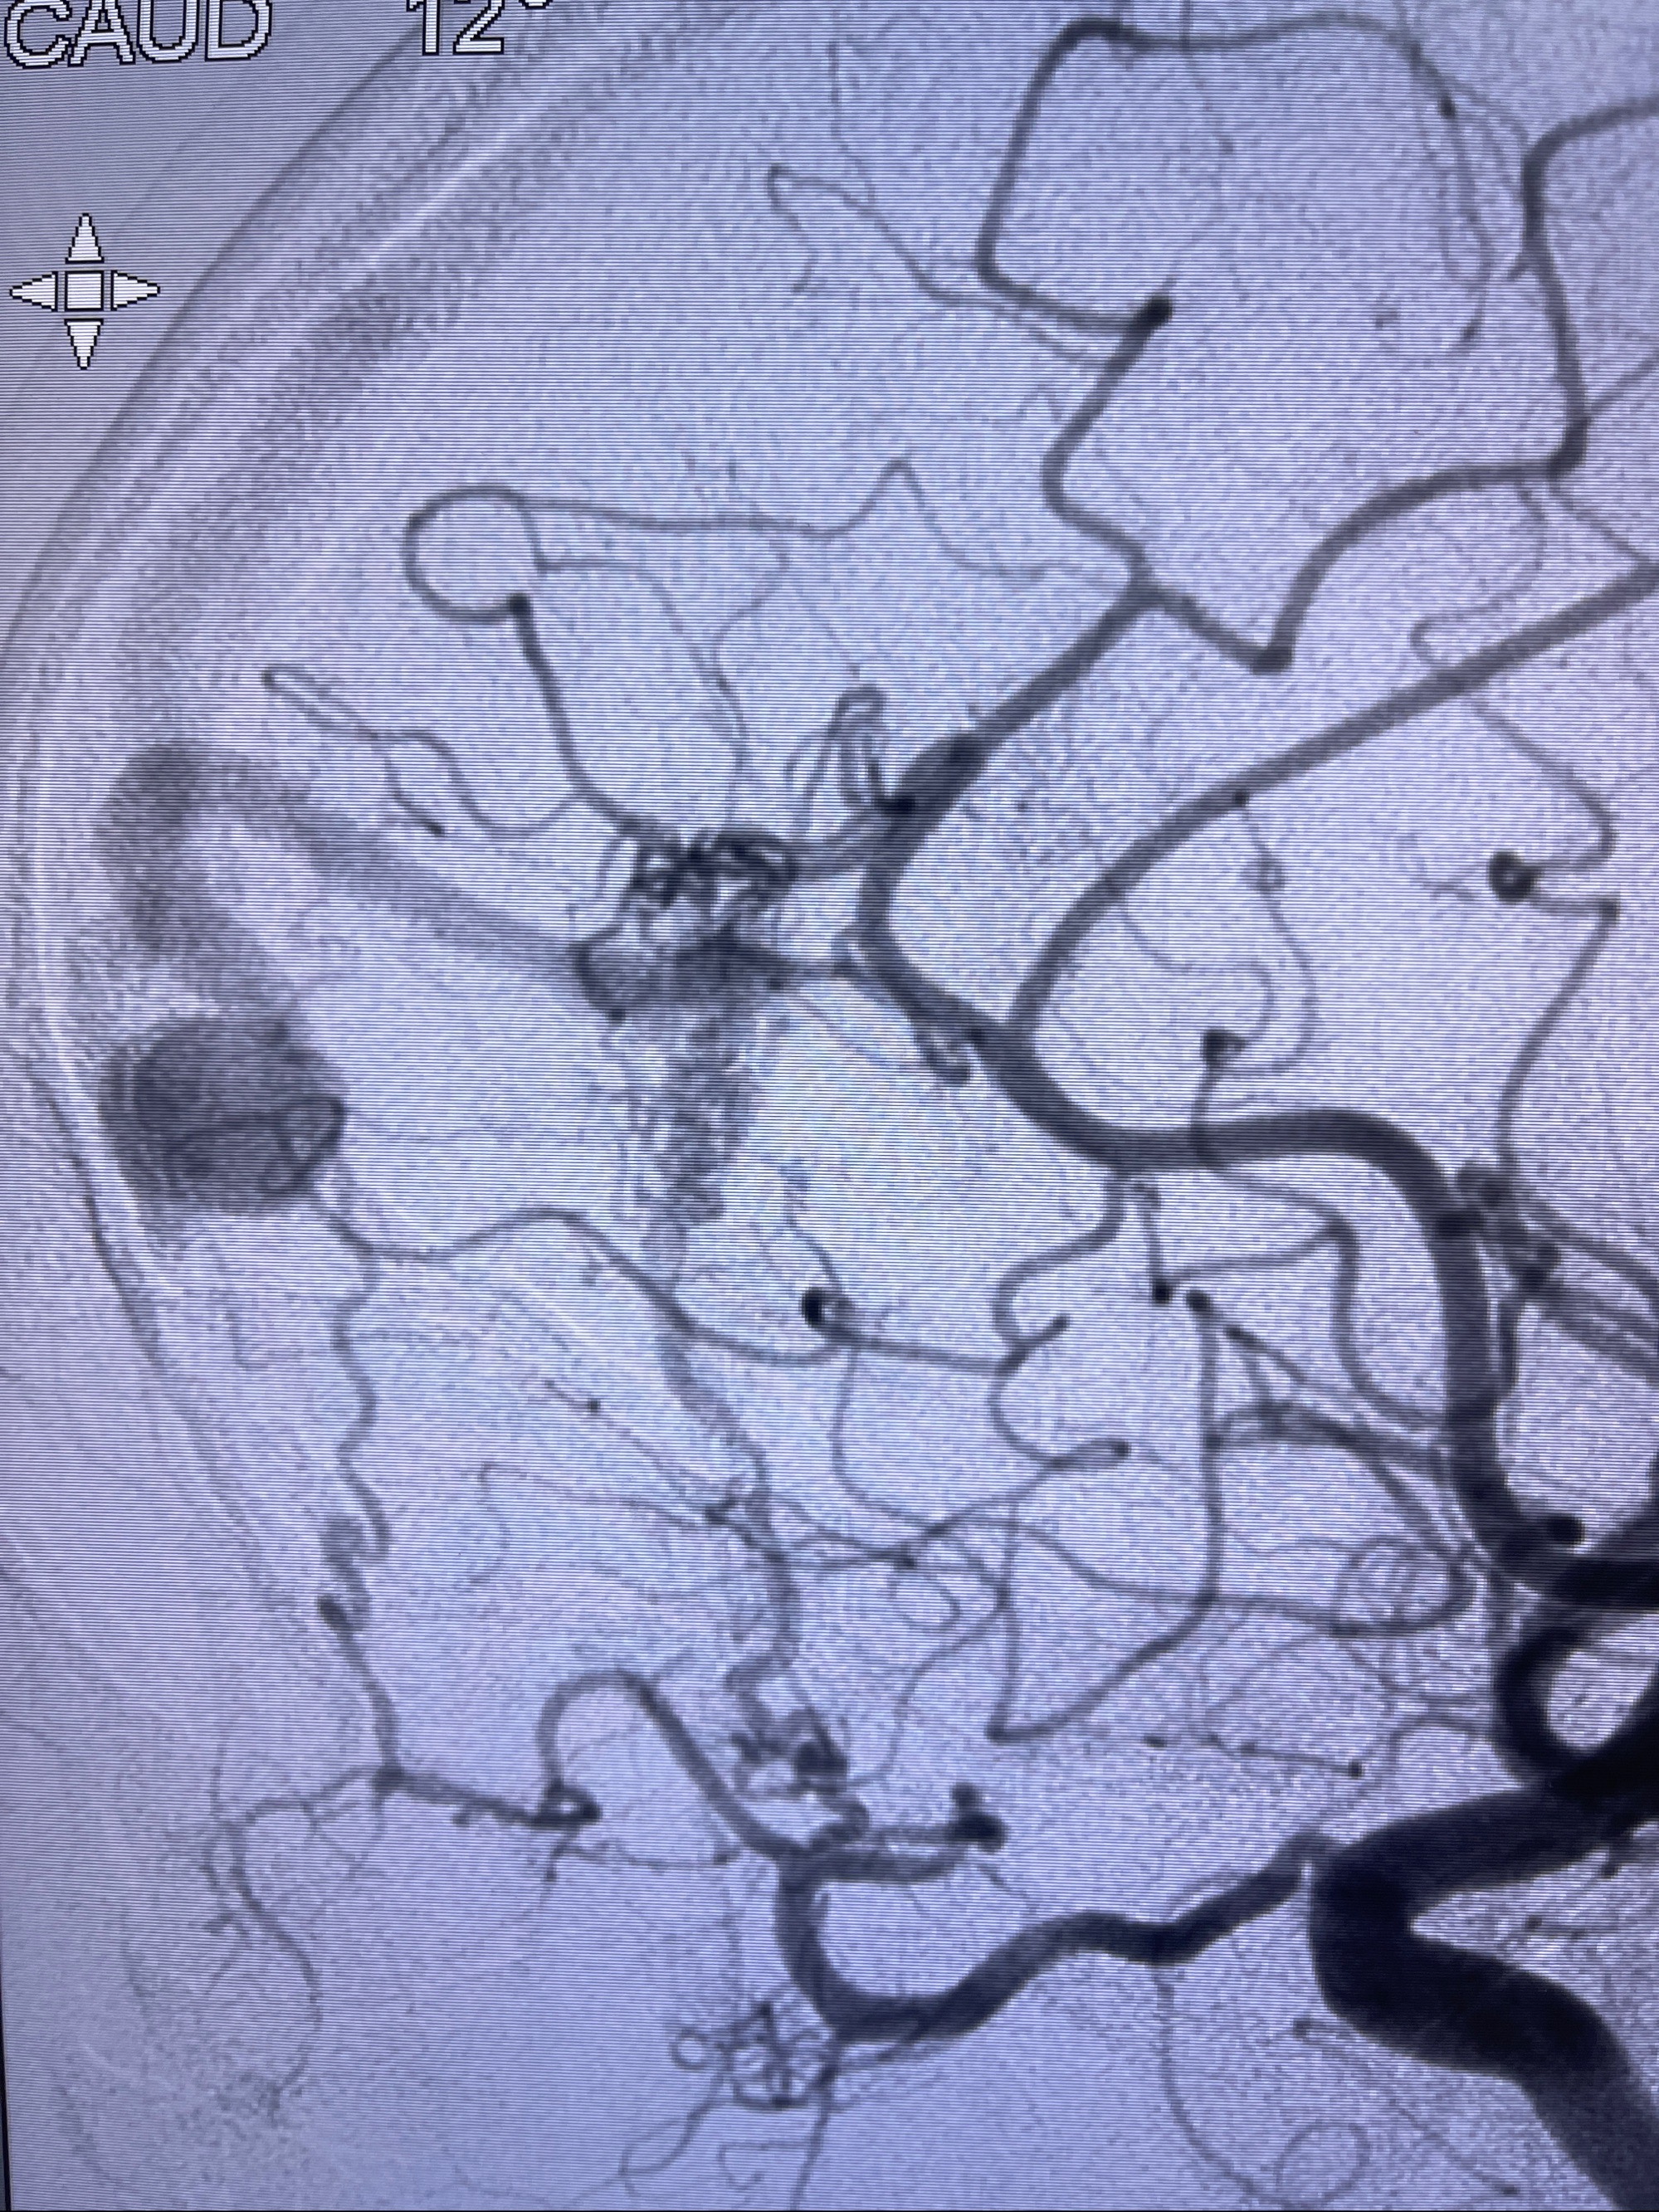

2023-09-13全脑血管造影:前颅底硬脑膜动静脉瘘,供血动脉为双侧胼周动脉、眼动脉脑膜支,静脉向上矢状窦方向引流

治疗策略:

- 外科手术?

- 介入干预:静脉途径栓塞or动脉途径填塞?